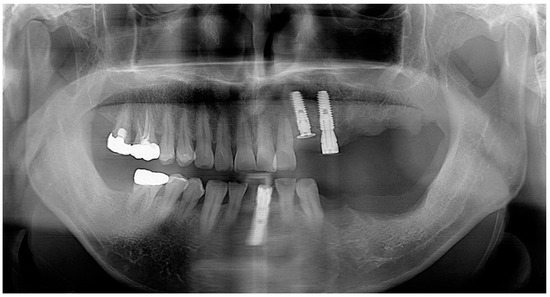

Utilization of Tenting Pole Abutments for the Reconstruction of Severely Resorbed Alveolar Bone: Technical Considerations and Case Series Reports

2. Case Presentations

- Woo, R.H.; Kim, H.G.; Kim, G.; Park, W.E.; Sohn, D.S. Simplified 3-dimensional ridge augmentation using a tenting abutment. Adv. Dent. Oral. Health 2020, 12, 185–205. [Google Scholar]

- Sohn, D.S. Reconstruction of three-dimensional alveolar ridge defects utilizing screws and implant abutments for the tent-pole grafting’ techniques. In Essential Techniques of Alveolar Bone Augmentation in Implant Dentistry, 2nd ed.; Tolstunov, L., Ed.; Wiley Blackwell: Hoboken, NJ, USA, 2023; pp. 404–418. [Google Scholar]